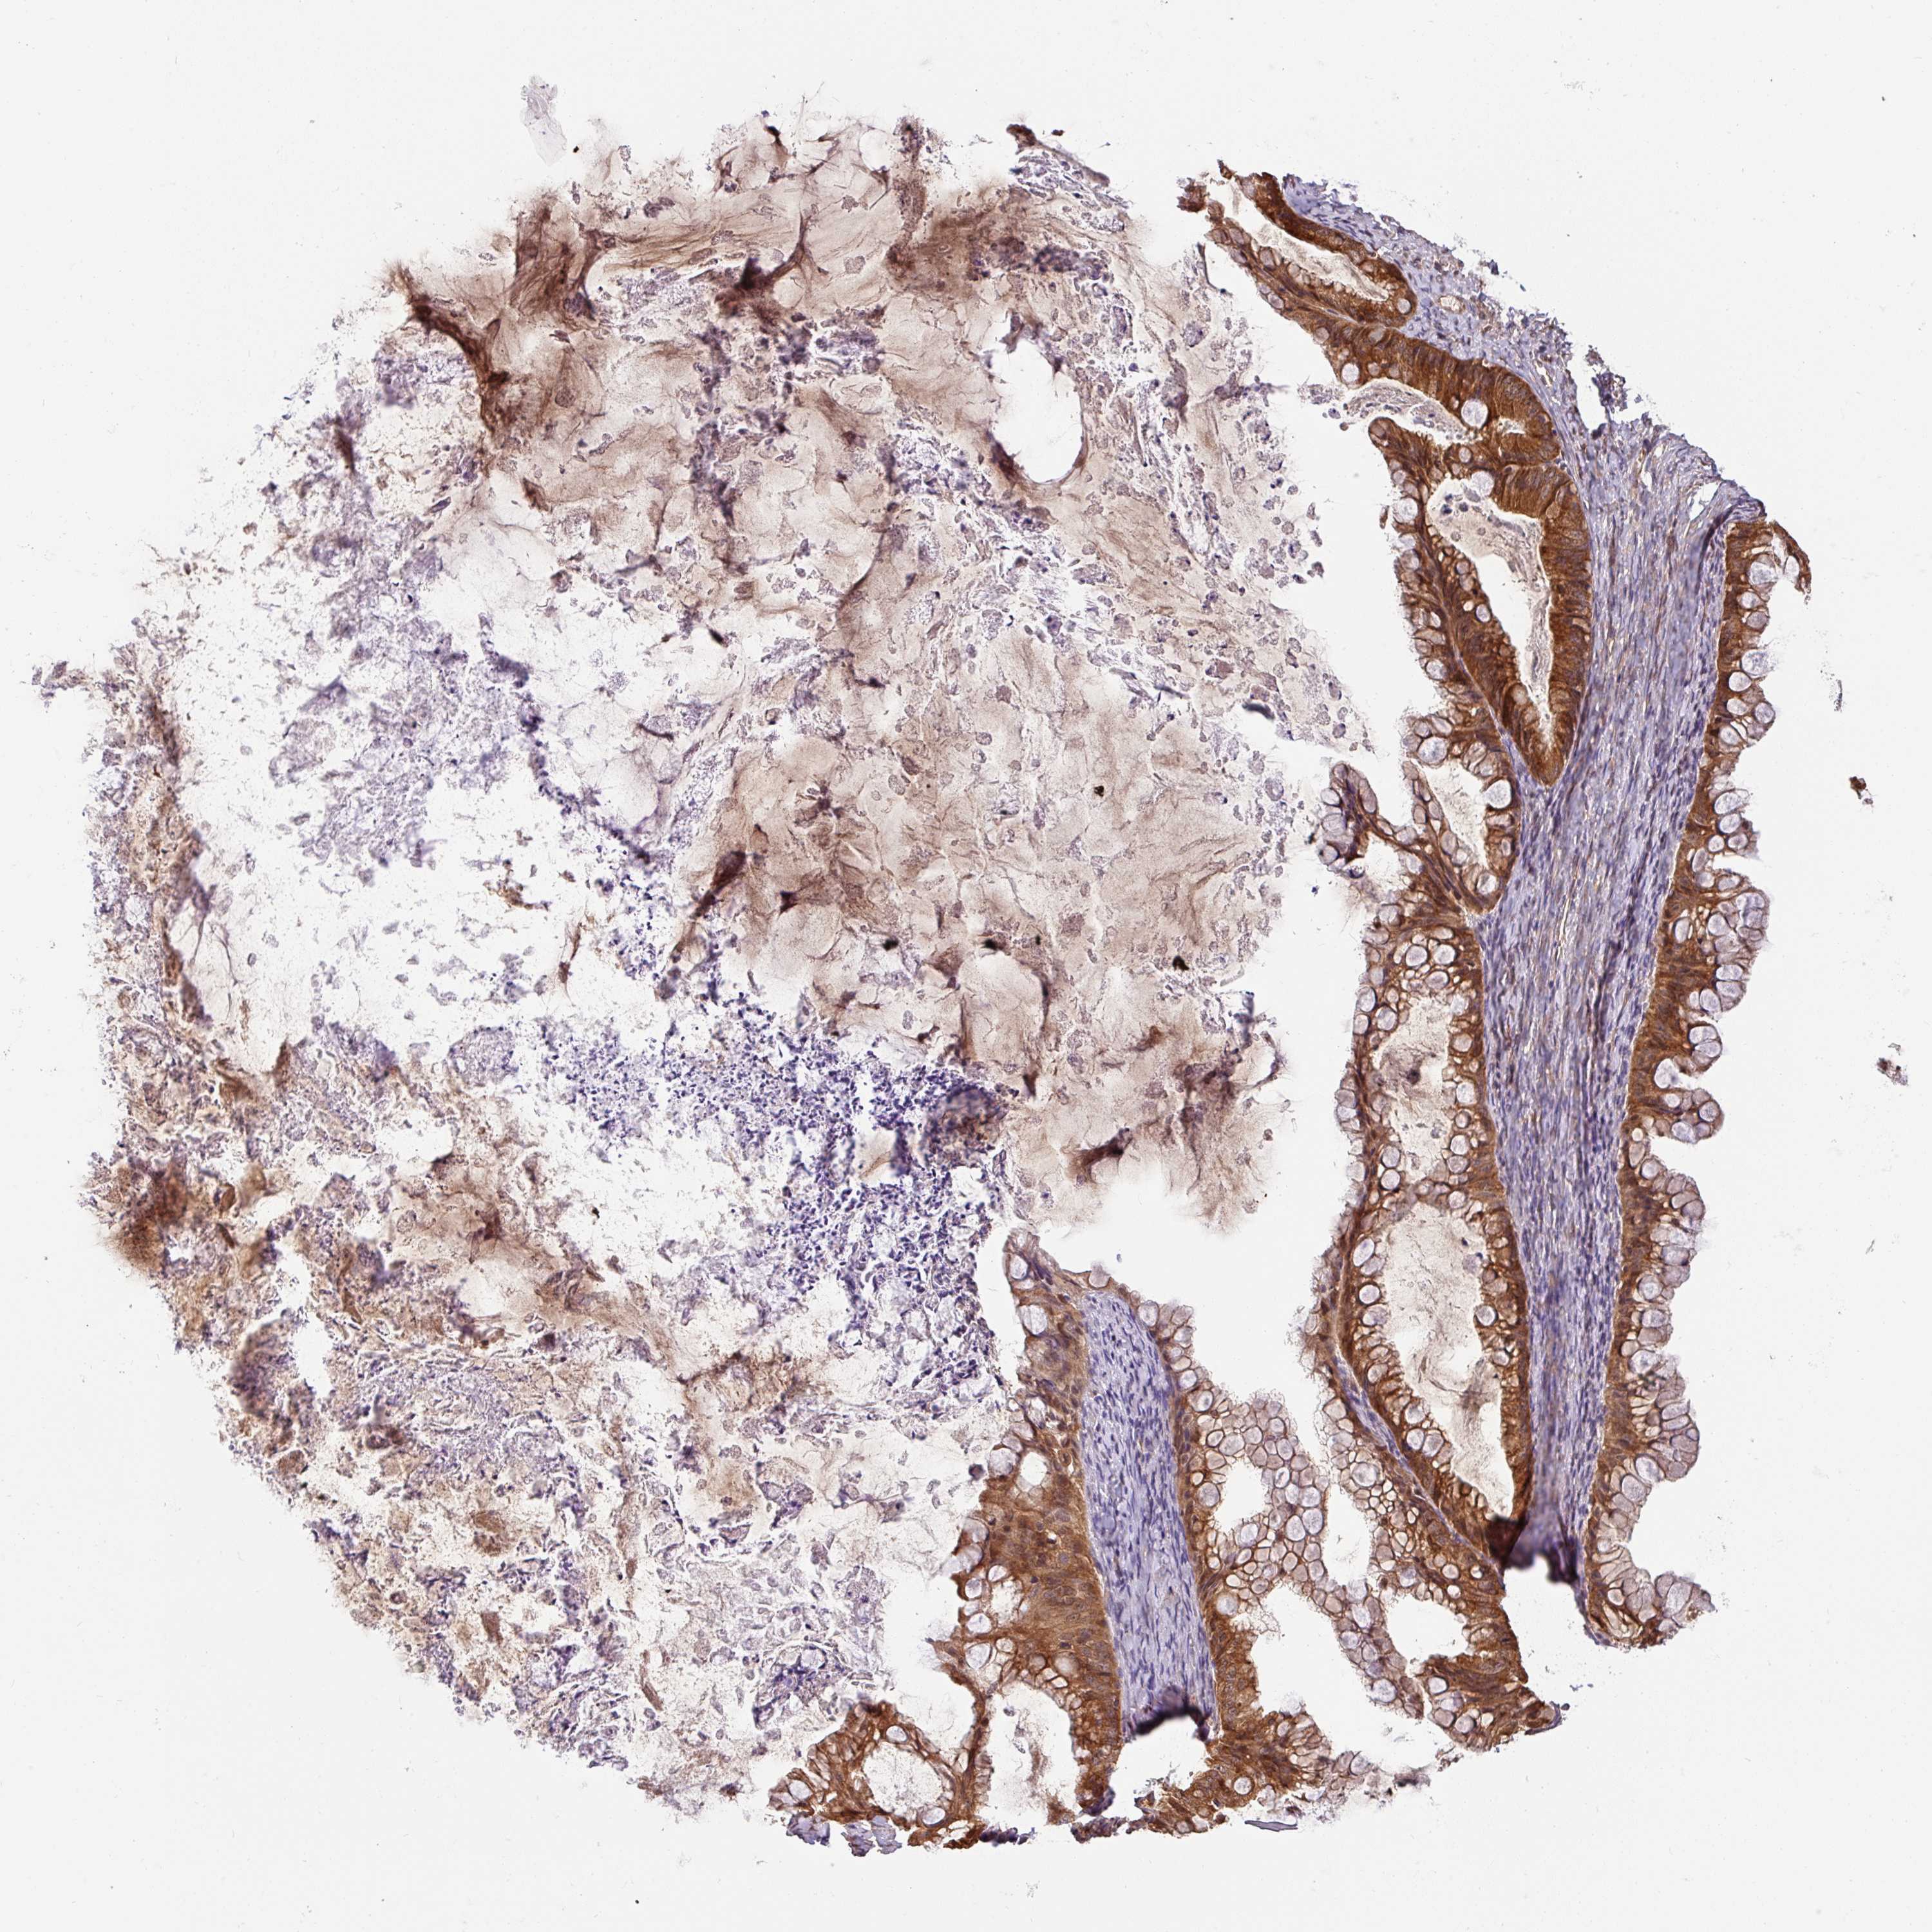

OVARIAN CANCER - Protein expressioni

A mouse-over function shows sample information and annotation data. Click on an image to view it in a full screen mode. Samples can be filtered based on level of antibody staining by selecting one or several of the following categories: high, medium, low and not detected. The assay and annotation is described here.

Note that samples used for immunohistochemistry by the Human Protein Atlas do not correspond to samples in the TCGA dataset.

Antibody stainingi

Antibody staining in the annotated cell types in the current human tissue is reported as not detected, low, medium, or high, based on conventional immunohistochemistry profiling in selected tissues. This score is based on the combination of the staining intensity and fraction of stained cells.

Each image is clickable and will lead to virtual microscopy that enables deeper exploration of all samples and also displays staining intensity scores, fraction scores and subcellular localization as well as patient and tissue information for each sample.

Antibody HPA049911

Antibody CAB010161

Cystadenocarcinoma, serous, NOS

Cystadenocarcinoma, mucinous, NOS

Adenocarcinoma, NOS

Carcinoma, endometroid

Carcinoma, NOS